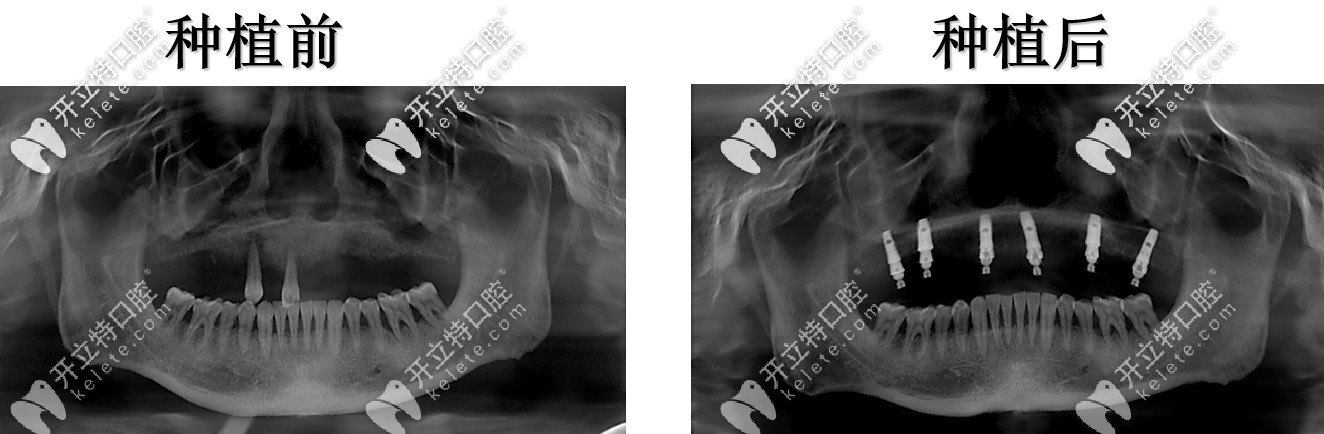

半口種植術前術后對比

這次種牙沒有受太大的罪,有點幸運,也幸虧了女兒天天在我跟前念叨讓我去整牙看看,有一個術前術后的照片對比,我覺得沒啥變化,但是裝上牙確實是感覺挺好,吃東西的感覺又回到了滿口真牙的時候。

種植牙前后對比

本來上面還有兩顆牙齒的,結果給我設計方案的王凌成醫(yī)生說,上面松動的牙,沒有必要保留了;然后建議種六顆半口恢復,想了想覺得還行,然后就做了性價比相對比較高的德國ICX種植體,網(wǎng)上也搜了搜,德國這個進口種植體在口腔技術這一塊算是先進品牌,這才放心地做...

上半口六顆種植恢復